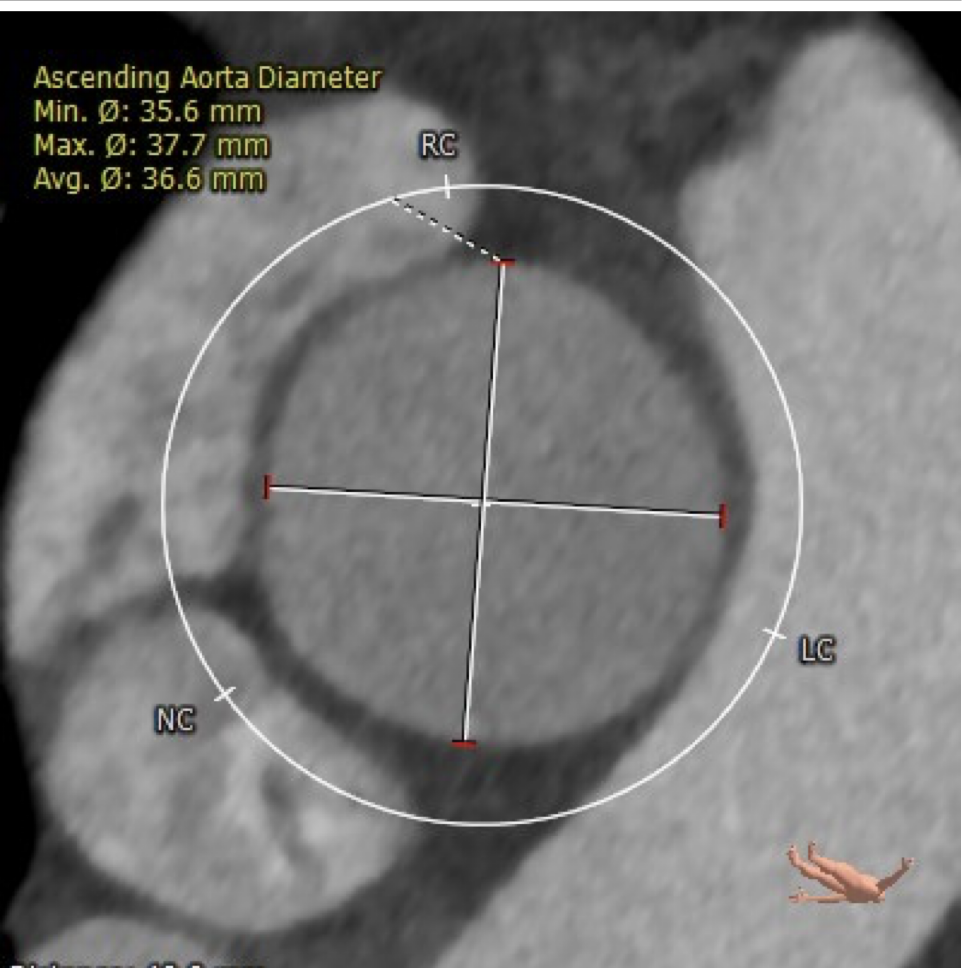

CT评估

升主动脉直径:36.6mm,心脏夹角:49度